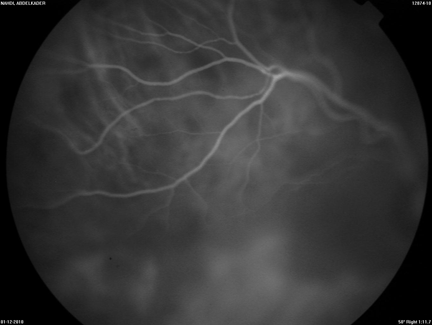

A 63-year-old man presented with blurred vision and a progressive loss of visual acuity for approximately two weeks. Medical history was remarkable for infiltrating breast carcinoma with negative complete work-up, for which he has had mastectomy, radiation therapy and chemotherapy in 2009. Ophthalmic examination showed exophthalmos of the right eye without ptosis. Ocular motility was normal. Best corrected visual acuity was (BCVA) 3/10 on the right eye and 7/10 on the left eye. Anterior segment examination was normal on both eyes with no dense cataracts observed. Fundoscopy under pupil dilatation in the right eye revealed an ill-defined choroidal mass in the upper temporal arcade, impinging on the macula and surrounding the papilla. The mass was associated with pigment epithelium impairment and normal optic discs, without macular edema. Fundoscopy in the left eye did not reveal any tumor. Standardized B-scan ultrasonography of the right eye revealed a posterior, hyperechogenic tumor of the choroid with secondary retinal detachment associated with choroidal thickening (Figure 1). Indocyanine green chorioangiography (ICG) was unremarkable in the left eye, but revealed a tumor in the right eye (Figures 2, 3). Magnetic resonance imaging (MRI) revealed a right ocular expansive lesion with non-circumferential posterior choroidal thickening (Figure 4).

Figure 1: Standardized B-scan ultrasonography of the right eye showing a posterior, hyperechogenic tumor of the choroid with secondary retinal detachment associated with choroidal thickening.